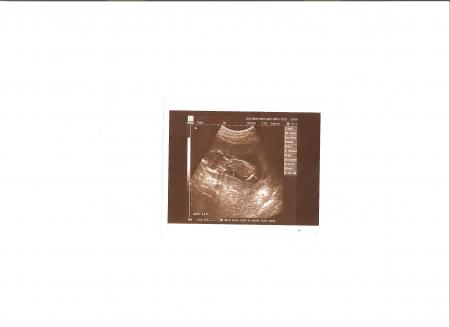

Вчера у меня было плановое УЗИ и за одно с тем же врачом договорились про УЗИ почек, чтоб все за один раз и лишний раз манюню не тревожить. На счет почек очень боялась, врачи напугали, но врач сказал все в норме. Слава Богу.

УЗИ я делала при роддоме, поэтому снимок мне не дали (у них нет этой аппаратуры, нет в ней необходимости), но муж снял нашу кроху на видео на своем телефоне! Я раз сто потом пересматривала, никак не могу насмотреться...

За день до УЗИ говорила с масюней, просила показать свой пол... Мое золото сделало мне подарок! Почти сразу мы повернулись так, что у врача даже сомнений не возникло... У нас с мужем будет ДОЧЕНЬКА!!!!!!!!!!!!!!!!!!!!!!!!!!!!!!!!!!!!!!!!!!!!!!!!!!!!! Она такая красивая!!!!!!!!!!!!!!! Она активненькая, плавает, маму стала пинать чаще, крупненькая...